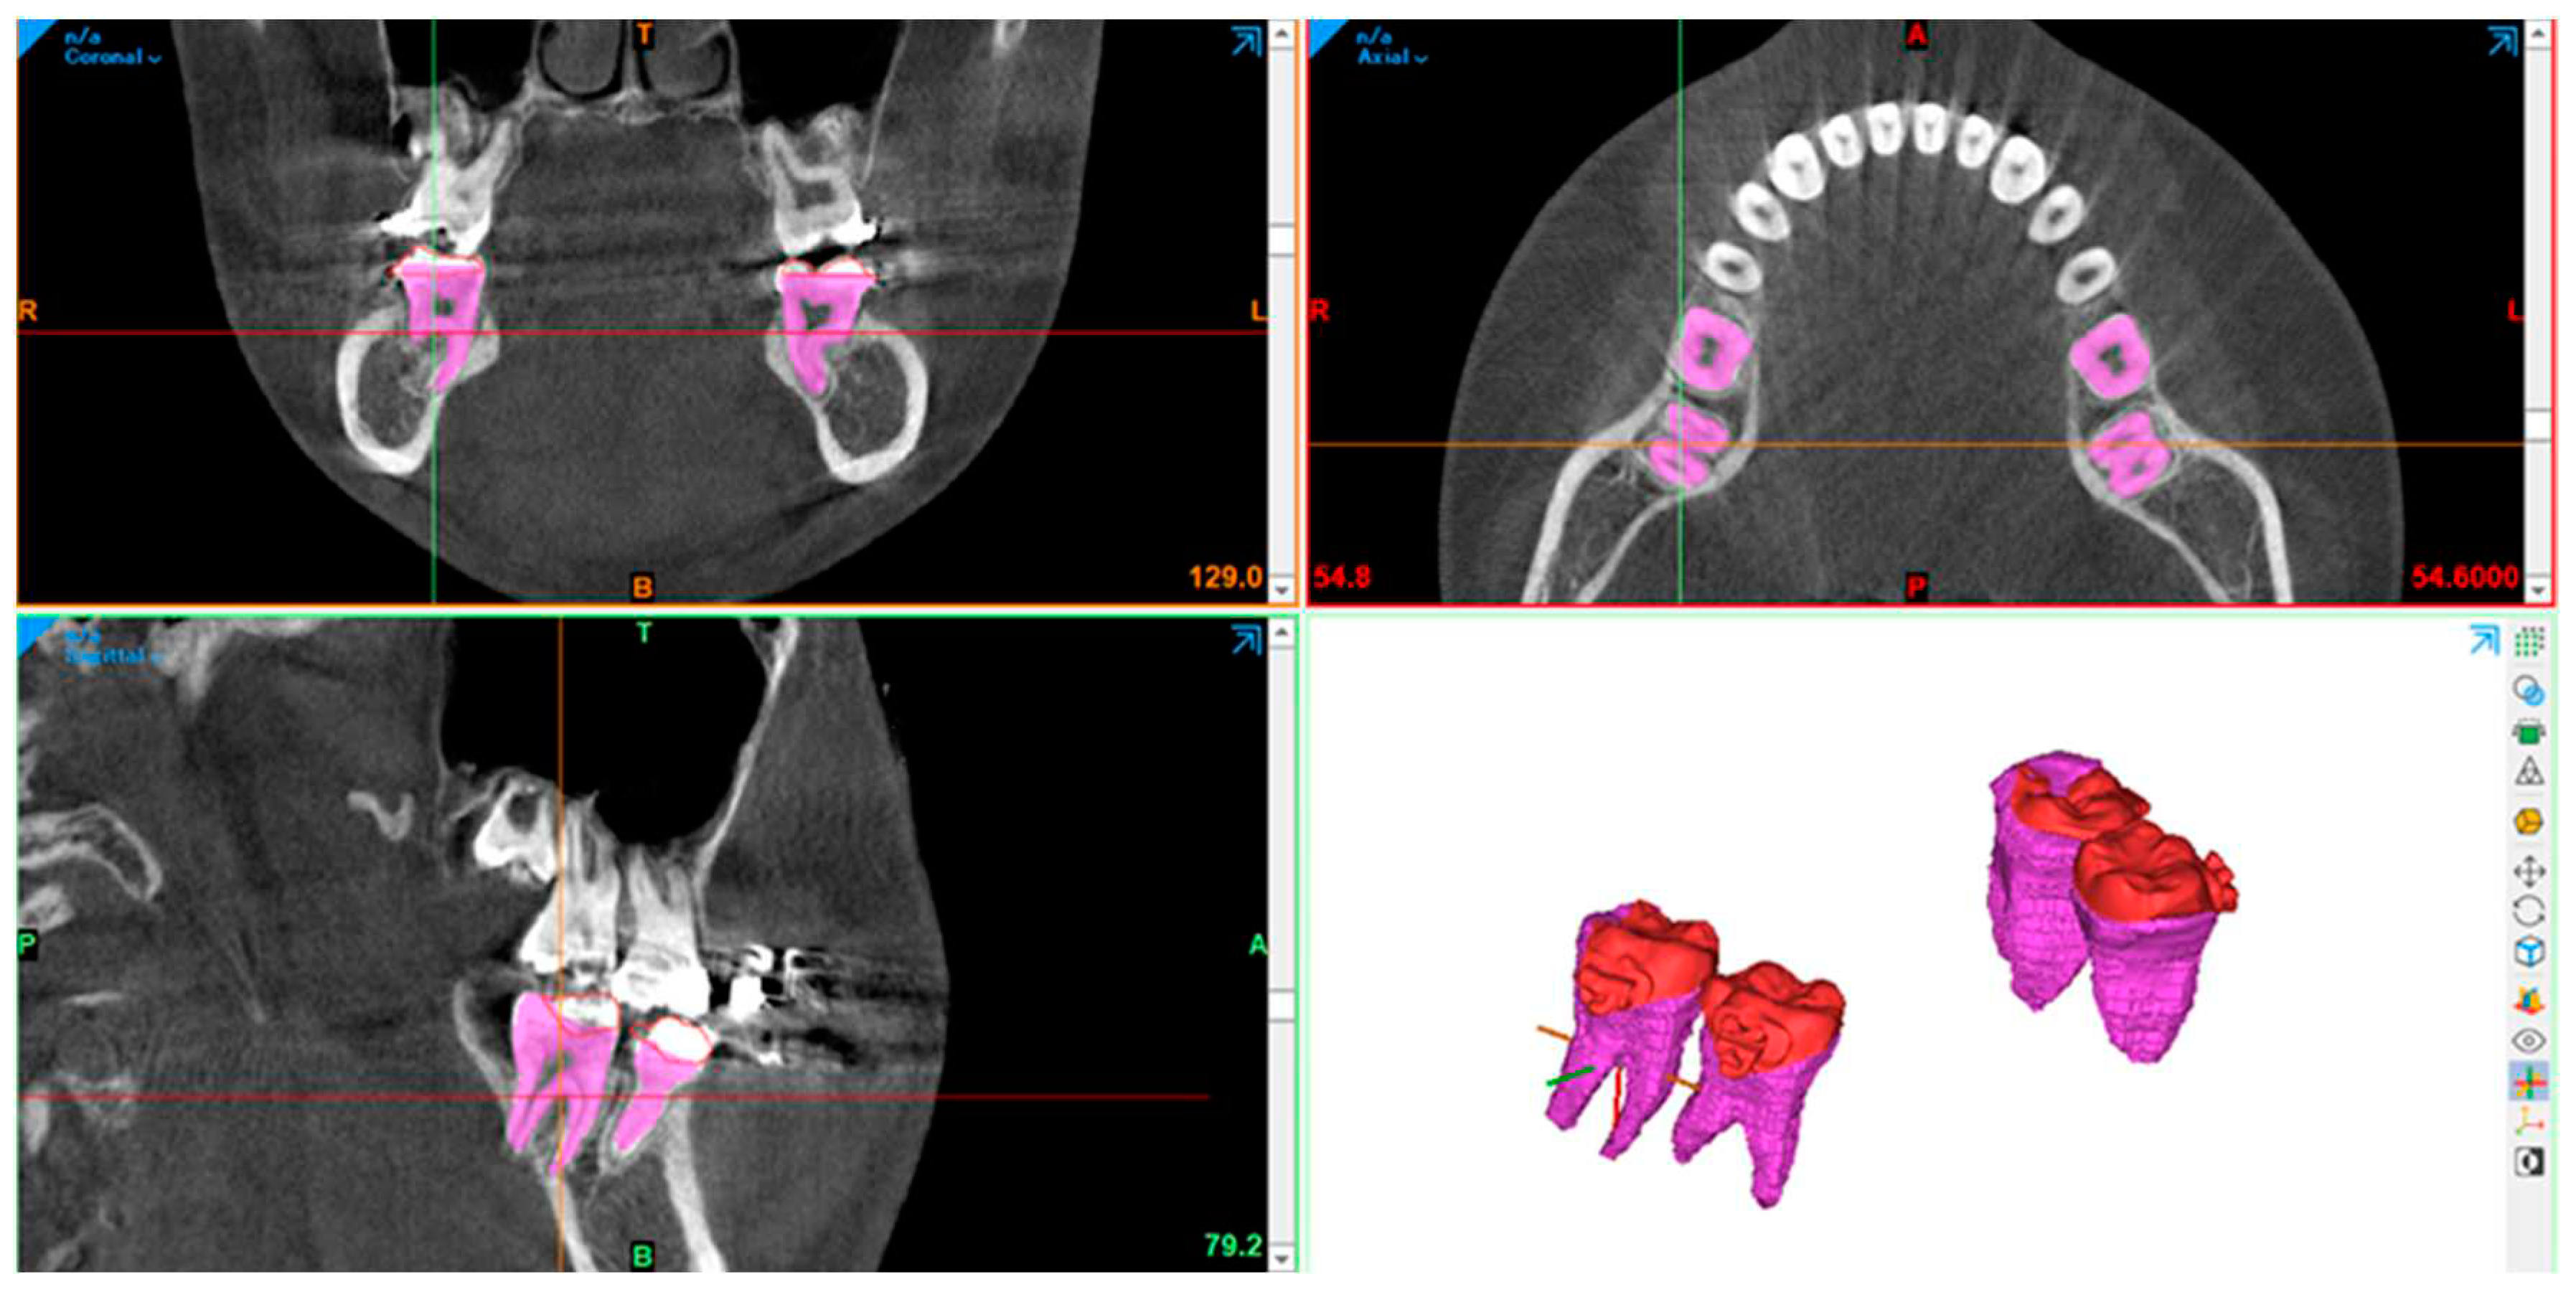

- The 3-Shape software completes the process of designing a surgical guide. By utilizing software, the diameter of the drilling bur and screw holder can be determined, ensuring no contact with the roots during the procedure. The 3-shape software simulates the screw placement within the bone's anatomic area. This simulation helps determine the tube design required for drilling and screw implantation.